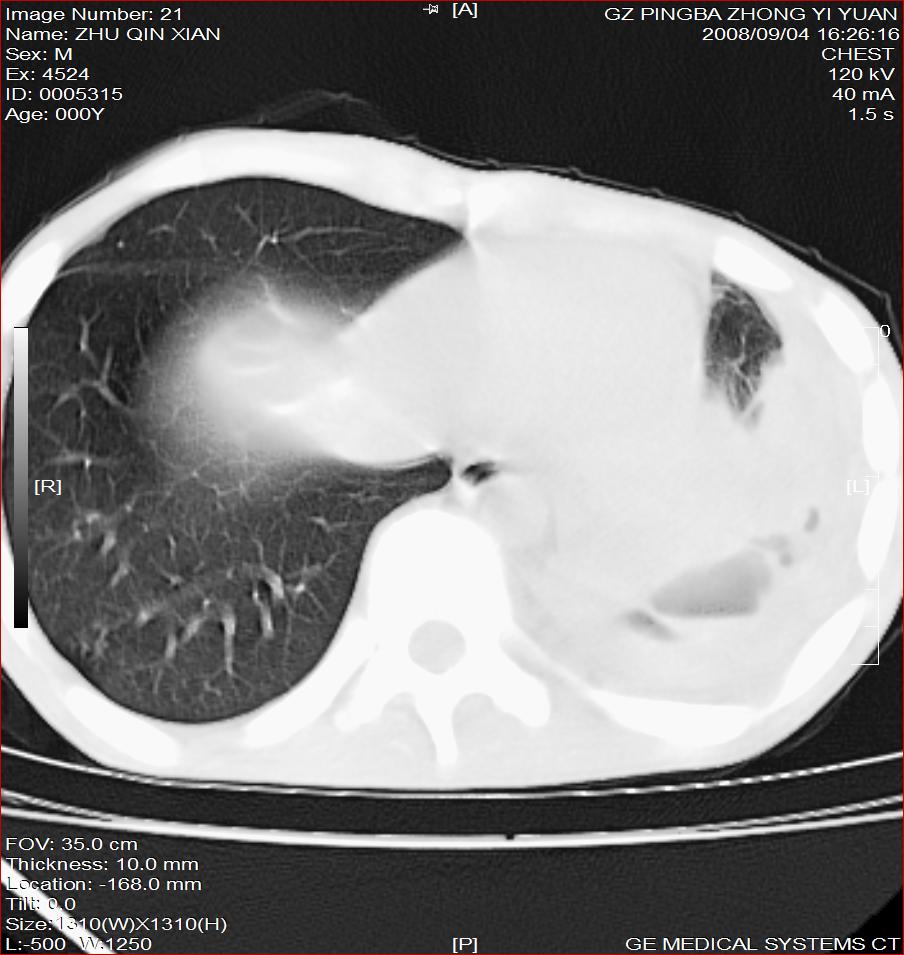

以下是引用随光逐影在2008-9-4 20:05:00的发言:[br]1)考虑两肺结核。2)左侧胸膜炎(胸膜肥厚、粘连,胸腔积液)。3)左侧局限性气胸。

以下是引用子十在2008-9-4 19:34:00的发言:[br]左上肺结核并空洞及双肺播散。节段性肺不张、胸腔积液、胸膜肥厚粘连。[br]